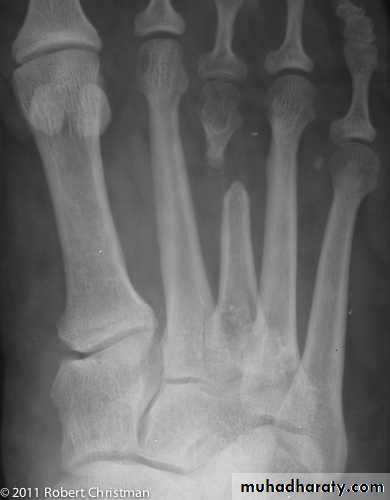

Avascular necrosis :

Certain regions are problematic for their tendency to develop ischemia and bone necrosis after injury.They are:

- the head of the femur (after fracture of the femoral neck or dislocation of the hip);

- the proximal part of the scaphoid (after fracture through its waist);

- the body of the talus (after fracture of its neck).

Accurately speaking, this is an early complication of bone injury, because ischemia occurs during the first few hours following fracture or dislocation.

However, the clinical and radiological effects are not seen until weeks or even months later.

Clinical features of AVN :

Painincreased bone density in the radiography

Treatment :

Femoral head AVN – total hip arthroplasty or arthrodesis

Scaphoid or talus – conservative treatment or joint arthrodesis